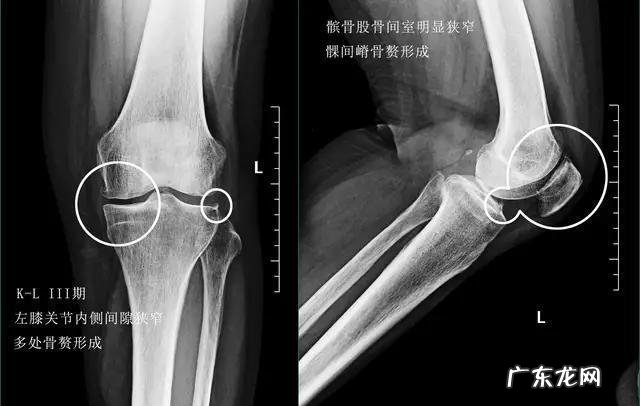

老人出现膝关节骨关节炎后还能锻炼吗?关节炎是很多老人经常谈及的一个疾病,有时老人之间唠嗑,谈到某一位老人膝盖疼的话,其他人都会问:“你是不是关节炎了?”,其实关节炎可以说是多种疾病的统称,包括骨关节炎、痛风性关节炎、风湿性关节炎以及类风湿性关节炎等等很多的关节炎都可以归类为关节炎这三个字,日常生活当中很多老年人口中的所谓关节炎,其实应该是骨关节炎 。骨关节炎主要的病理基础是关节内的软骨磨损、退变而导致关节出现骨质增生、骨刺的形成 。

因为当关节内的软骨发生磨损以后,骨与骨之间承受的压力就会有所改变,而我们的身体为了更好的减少骨头之间承受的压力,就会想方设法的增加骨头的面积,于是骨赘开始出现了,所以少量的骨质增生是帮助我们的,但如果软骨磨损的越来越重,骨赘也就是骨质增生形成的越来越多,刺激到了关节这边的组织就会导致各种各样的症状,病情严重的情况甚至会导致关节畸形,影响患者的膝关节的屈伸功能,造成长久的疼痛 。

症状:早期的膝关节骨关节炎患者往往会表现出膝关节后方的紧张感,在久坐或者是久站以后,膝关节有明显的不适,而疼痛并不是特别的严重,有些患者在夜深人静的时候屈伸膝关节是可以听到响声,但并不会有明显的痛感,在过度劳累的时候可能会出现膝盖的疼痛,但是休息以后就会有明显的减轻,另外还有很多老人会出现上下楼梯时关节的疼痛,但走平路往往非常正常 。诊断:早期的膝关节骨关节炎可以通过x线或者是核磁检查来明确诊断,当骨赘形成的不是非常多的时候,通过核磁检查可以早期的发现关节内是否存在软骨的磨损,从而进行早期的干预,比如口服氨糖等措施 。还能锻炼吗?在这个阶段是完全可以进行体育锻炼的,只是要注意运动的量和运动的时间,比如平时通过快走来锻炼身体,那么尽量要注意行走的步数,控制在8000到1万步就可以了,而且不要一次性走完,因为长时间的行走会造成关节周边肌肉、筋膜的紧张,会加重骨关节炎的病情,分次行走可以起到同样的运动效果,而且不会造成关节周边的负担 。另外游泳、打太极拳、骑自行车也都是可以的,同样注意量 。●中期的膝关节骨关节有什么样的症状,可以锻炼吗?